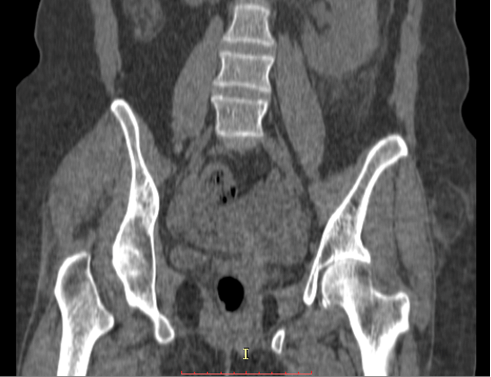

A 72-year-old female had a history of left hip trauma after tripping and falling at home. She was brought immediately to the emergency department and an anterior-posterior hip X-ray was done (Figure 1). As seen in the X-ray there was no sign of fracture but the clinical examination revealed pain at the left hip and limited mobility. Thus, considering the age of the patient, a pelvic CT scan was requested which also revealed no injury to the left hip (Figure 2). The patient was discharged and left home with anti-inflammatory and pain medication, being programmed to return after 7 days for a follow-up.

Figure 2: Computed tomography scan at the first presentation showing no fracture